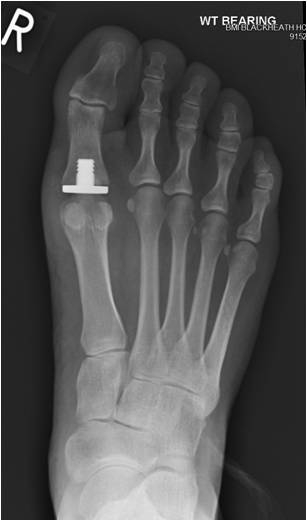

If the disease is more advanced either a joint fusion (arthrodesis)(Fig 3) or a joint replacement (Fig 4) can be considered. The former leaves the joint stiff but pain free, whereas the latter involves implanting an artificial joint which allows some joint movements whilst reducing or eliminating pain.

Big toe joint replacement surgery takes a similar amount of time to recover from, weight-bearing in a protective shoe is required for 4-6 weeks and toe exercises are started early.